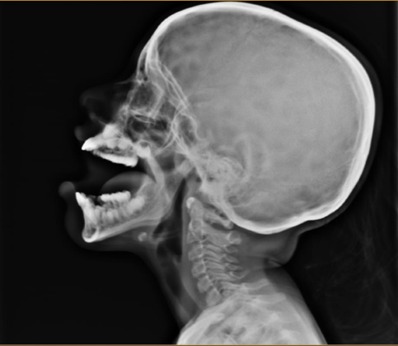

• Nasal endoscopy (a small camera to visualize adenoids) / X-ray of nasopharynx